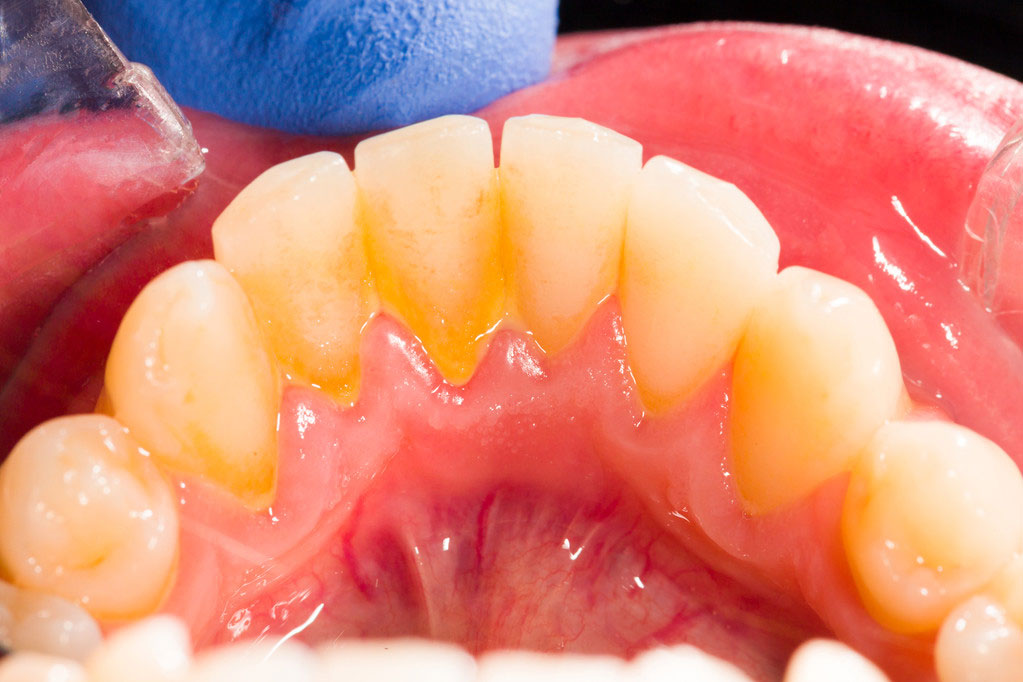

而已經發硬、摳不掉的黃色物質就是牙石,它是長期滯留的菌斑、軟垢與唾液中的礦物質結合后,逐漸鈣化形成的。如果有吸煙的習慣,它還會被着色變成棕色,甚至黑色。

牙石的形成就像滾雪球一樣:菌斑礦化后形成的粗糙表面為細菌安家提供了便利,新的菌斑沉積又礦化……牙石越變越厚,它的表面總有“新鮮”的菌斑在猖獗,而它本身也是多孔的,更加利於藏污納垢。此外,其吸附的細菌毒素還會不斷刺激它無辜的鄰居——牙齦,甚至進一步侵犯我們的牙周組織。